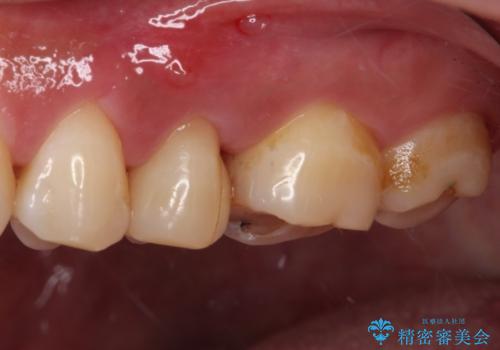

- 上下の歯が接触する度に痛みを感じるとのことで来院された患者様です。

診査の結果、既に歯の神経は失活しており、レントゲンより根尖部に病変を認めました。

根管治療を行った後にオールセラミッククラウンにて補綴することとしました。